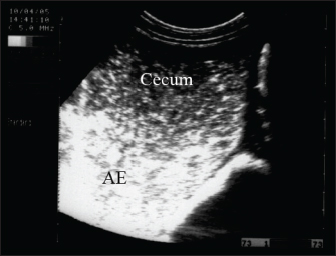

Fig. 11. Ultrasonography of a female donkey exhibiting sand colic. Case history included a recurrent episode of severe abdominal pain. Rectal examination revealed a large amount of sand in the feces. Abdominal ultrasonography shows cecal impaction with sand. Acoustic enhancement (AE) within the cecum was a characteristic sonographic finding.